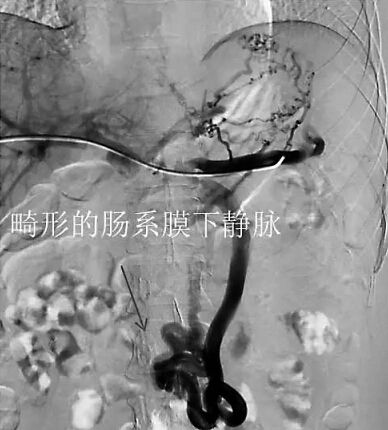

小林腹部的畸形静脉(医生供图)

在进行介入治疗的手术时,医生发现了真相:小林肚子里长了一条跟别人不一样的“蛇”形血管,这条畸形的肠系膜下静脉,形成了门体(门静脉与体循环)侧枝。而正常人的门静脉与体循环之间是没有这个异常的“天桥”。由于小林怀孕后,孕激素增加导致血液高凝状态,与这个异常的“天桥”相互作用,进而引起门脉系统血栓。